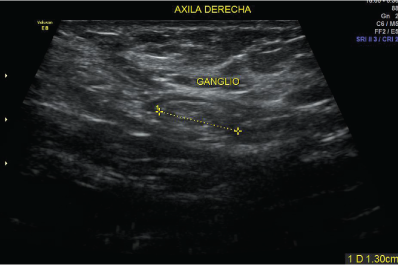

La ecografía mamario utiliza ondas sonoras para producir fotografías de las estructuras internas del seno.

Se utiliza primariamente para ayudar a diagnosticar bultos en el seno u otras anormalidades que su médico podría encontrar durante un examen físico, una mamografía o una RMN del seno.

Sus imágenes pueden ayudar a determinar si un bulto anómalo es sólido, si está llena de líquido o si es a la vez quístico y sólido.